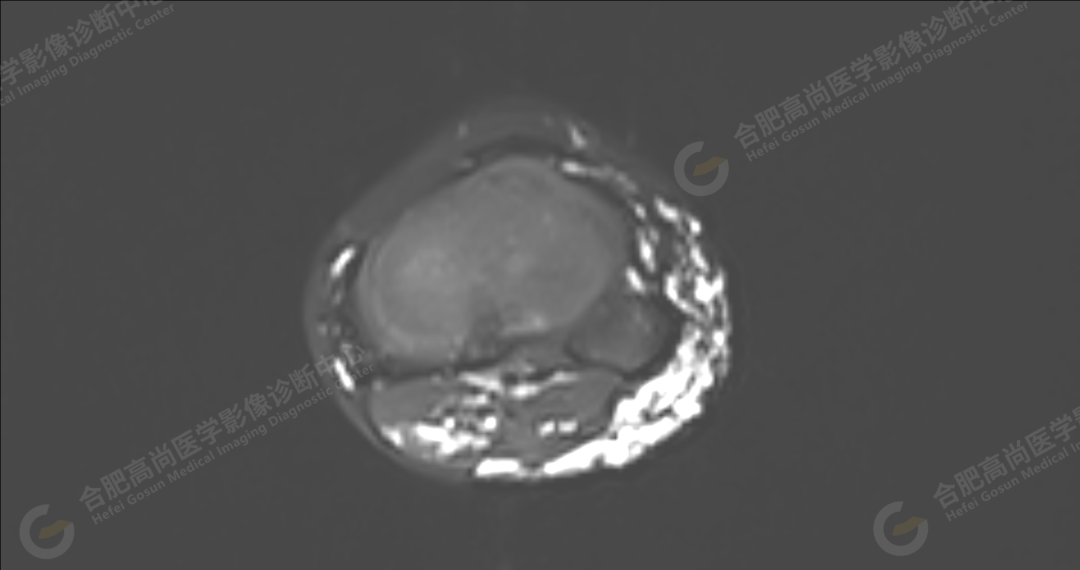

左侧髂骨内侧及闭孔内肌前方可见网格状异常信号影,边界欠清,T1WI 呈低信号,T2 压脂呈高信号,病变连续,延伸至臀肌内;左侧臀肌间隙及皮下、左大腿后部肌肉群及皮下、左膝前外侧及腘窝皮下、左小腿后侧皮下累及比目鱼肌及内外侧腓肠肌、左内外踝皮下、左足背足底及左足肌间隙内可见大片状、结节状弥漫性异常信号影,形态不规则,分布不均匀,边界不清,T1WI 呈低信号,T2WI 压脂后病灶呈高信号,部分病灶内可见网格状低信号,左足部肌间隙增宽,第 2-4 跖骨稍受压,骨质结构完整。左髋关节、膝、左踝关节间隙正常,无明显狭窄及增宽,关节面光滑,关节腔内无积液,左股骨、胫腓骨及踝部各组成骨骨质结构完整,未见明显异常改变。

左侧盆腔及下肢皮下及部分肌间隙内漫状血管瘤,请结合临床。